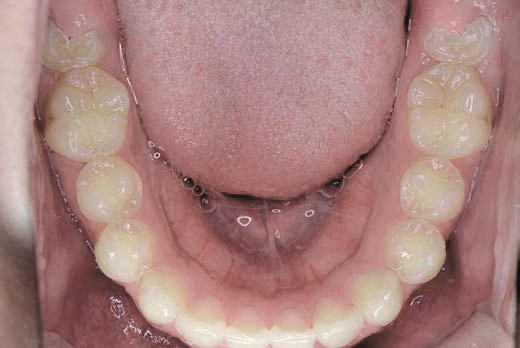

これから生えてくる永久歯のスペースがなく、歯が並ぶ余地がほとんどありませんでした。

さらに、上からあごの骨を見たところ、中央がくびれた“ひょうたん型”に変形しており、あごの成長にも偏りが見られました。

診断の結果、前歯の中心も少し左にずれており、特に犬歯が生えるスペースが足りない状態でした。

飲み込むときに下くちびるに力が入り、顔の左側にゆがみが出ている様子も確認できました。

治療を終えて

犬歯が歯ぐきの中に埋まっていたため、透明のマウスピース型装置で生えるスペースを作り正しい位置に導きました。もちろん抜歯せずに歯並びを整えることができました。お口の中がとても小さく、型どりの際にオエッとなる反応が強く、当時は装置を作るのが大変でした。しかし現在では3Dスキャナーと3Dプリンターを活用しスムーズに治療できます。

主訴・治療内容 「あごが小さいから、歯がきれいに並ばない」と他院で言われ永久歯を抜く矯正をすすめられていました。

本当に非抜歯で治療できるのか心配されていましたが、治療方法を丁寧にご説明し、お任せいただきました。

治療期間 5年

費用 550,000円(税込)